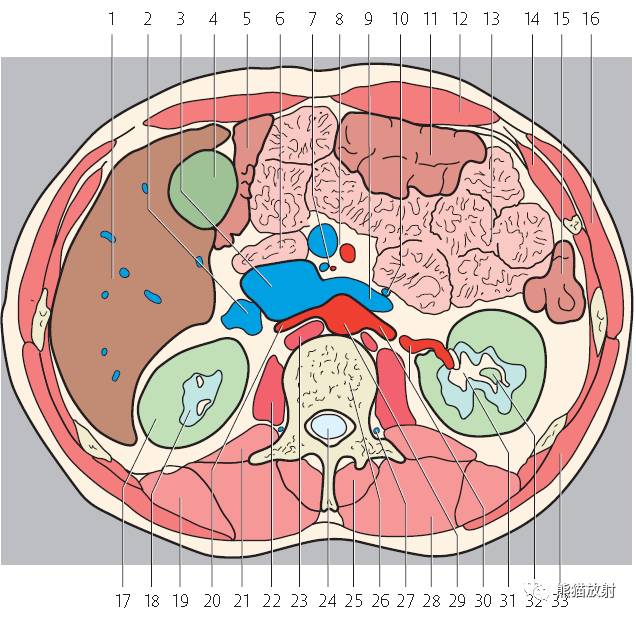

第二层

腹腔(粉色);腹膜后(黄色)

1、肝右叶;2、下腔静脉;3、肝尾状叶;4、肝门静脉;5、肝左叶;6、胃左动脉;7、腹直肌;8、膈肌;9、胃;10、结肠左曲;11、腹外斜肌;12、胸导管;13、奇静脉;14、腹主动脉;15;胸椎;16、最长肌;17、椎管和脊髓;18、棘肌;19、髂肋肌(胸段);20、脾脏;21、左肺;22、背阔肌;23、肋膈隐窝;24、右膈下隐窝;25、肝裸区;26、膈上淋巴结;27、肋间淋巴结;28、后纵隔;29、膈下淋巴结;30、左侧结肠旁沟。